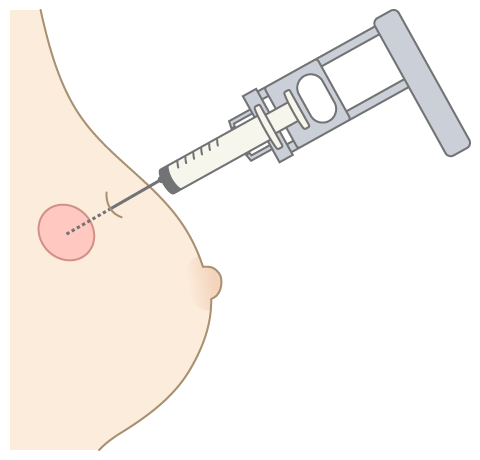

穿刺吸引細胞診

穿刺吸引細胞診

細胞診では、しこり(腫瘍)から吸引した細胞や乳頭からの分泌物を顕微鏡を使って観察します。細胞を吸引する際には、細い注射針を使用します。超音波(エコー)を使い、しこり(腫瘍)の位置を画面で確認する場合もあります。